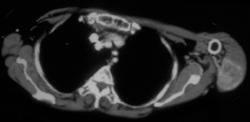

Radiofrequency Ablation (RFA) of Osteoid Osteoma